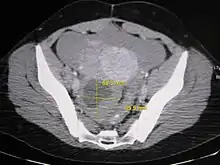

Further work up involves imaging, such as a pelvic ultrasound or CT scan.[7] Theca lutein cysts with diameters over 6 cm in size can be seen through these imaging modalities.[18] Benign ovarian cysts and complex cysts that are potentially malignant are distinguishable via ultrasounds.[19] Labs are also collected to evaluate leukocytes and tumor markers, such as beta-hCG and cancer antigen 125 (CA125).[20]

During pregnancy, ultrasonography is the first-line method for evaluating ovarian cysts. Both transabdominal and transvaginal route of ultrasonography are used with either two-dimensional or three-dimensional modalities.[3] Two-dimensional is more common, but three-dimensional can offer more results.[3] Doppler ultrasonography can also be used and is helpful at analyzing the characteristics of the cyst.[3] It can identify the presence of color flow within a septum as well as the presence of a solid component of the mass.[3] Ultrasonography is an effective tool for observing the progression or regression of the cyst.[3] Magnetic resonance imaging (MRI) is the second-line method used when ultrasonography cannot detect the cyst.[3] Cysts that are too large to be accurately analyzed by ultrasonography are typically when MRI would be used.[3] The advantages of MRI are its larger field of view and multiplanar capabilities.[21] In addition, pathologies such as infarctions and placental invasive disorders can be seen more clearly.[3] MRI is especially beneficial in gestational age and obese people.[3] MRI is also beneficial at preventing the exposure of ionizing radiation to the fetus during pregnancy.[22] Both ultrasonography and MRI show enlarged ovaries with multiple theca lutein cysts.[3]